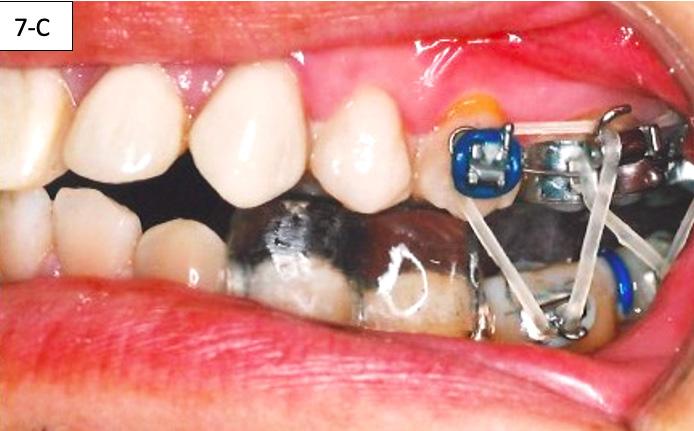

After the patient became accustomed wearing the splint, the acrylic was cut off distally to #46(30) and #36(19). A band was cemented on #17(2), #16(3) and #27(15), #26(14) and brackets/ tubes were bonded on #15(4), #25(13), #37(18), and #47(31). A 016 SS sectional wire was inserted in the maxilla bilaterally from the second molar to the second bicuspid and a ¼” - 4.5 oz elastics were placed for forced eruption of the mandibular second molars (Figure 7-A, B).

When the mandibular second molars became in contact with the maxillary molars, the acrylic was hollowed out from the intaglio of the splint above #46(30) and #36(19). Two ¼” –4.5 oz triangular elastics were placed for forced eruption of the mandibular first and second molars (Figure 7-C, D).